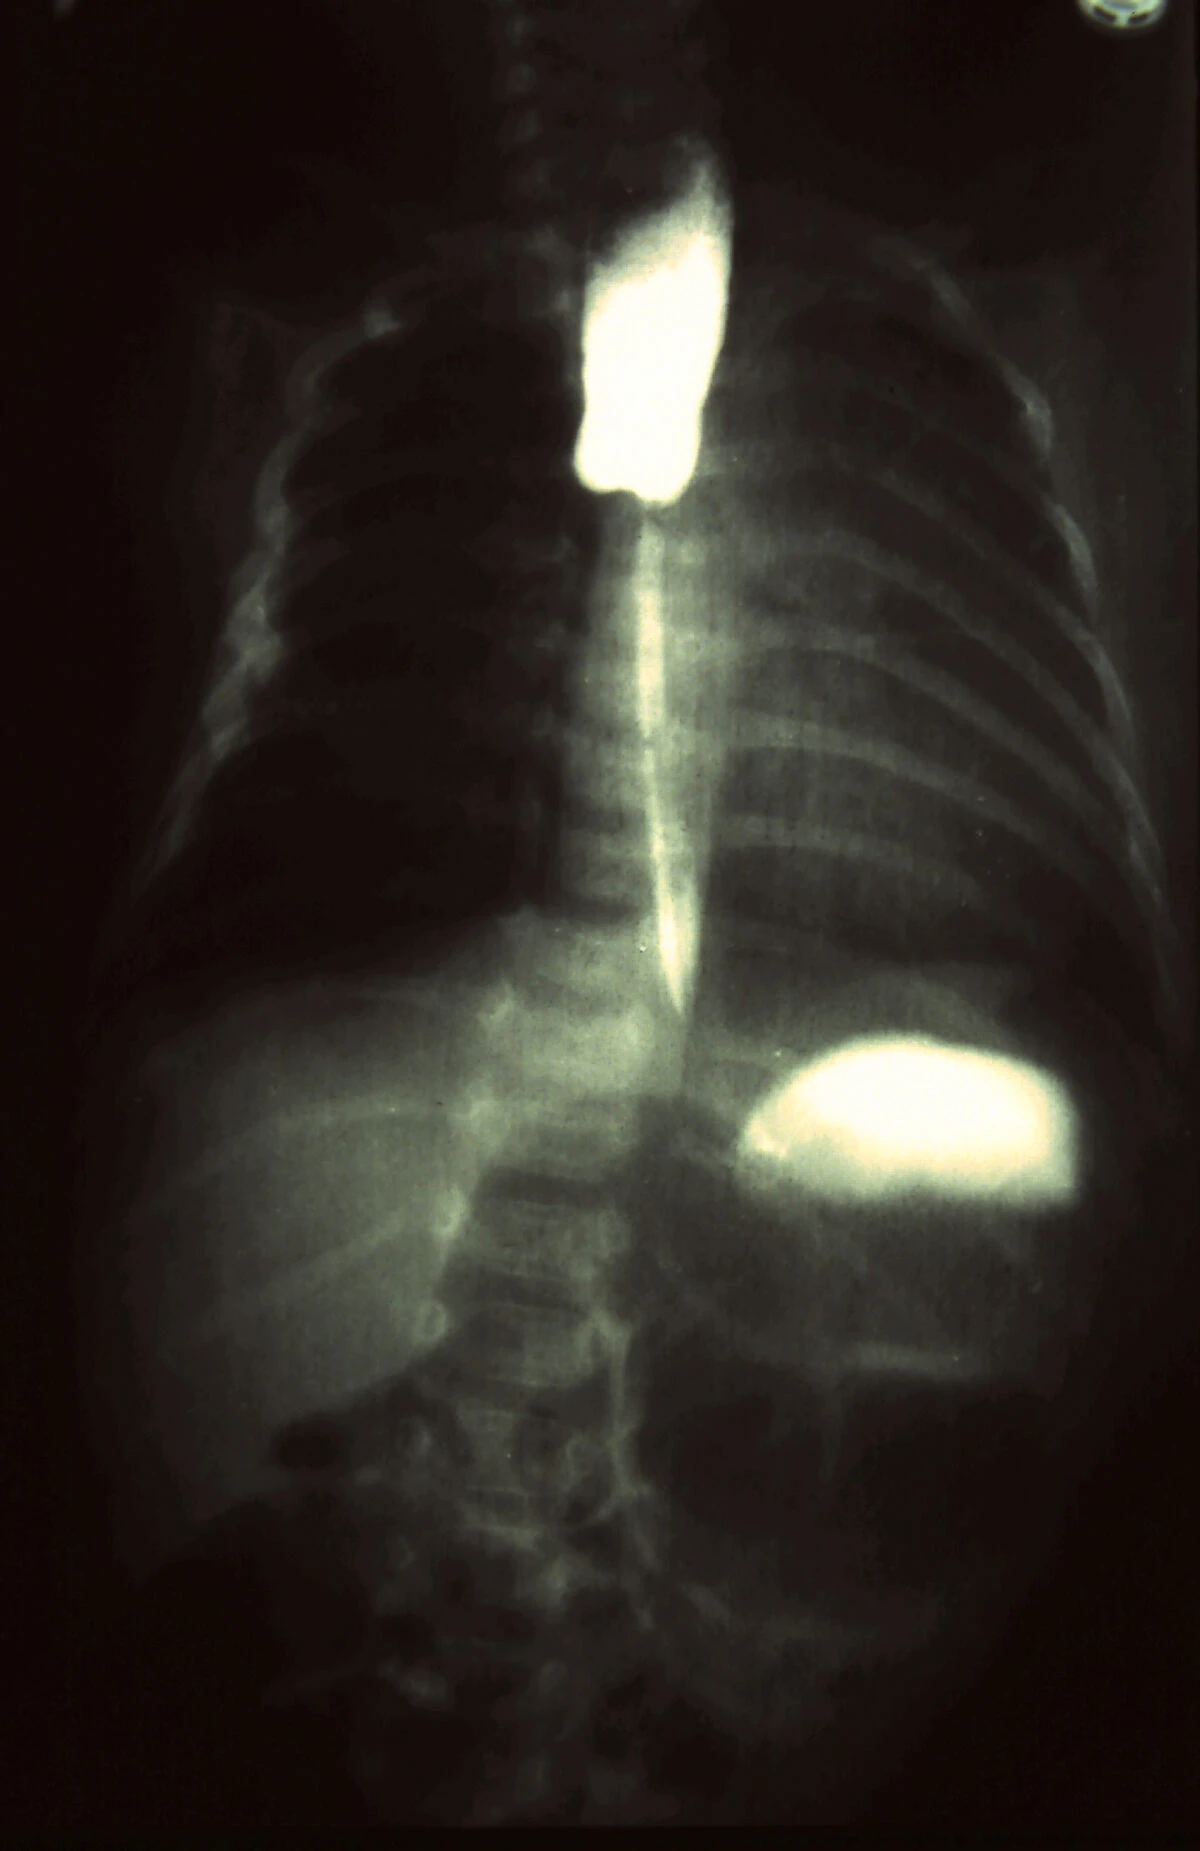

- Atresia esofagea